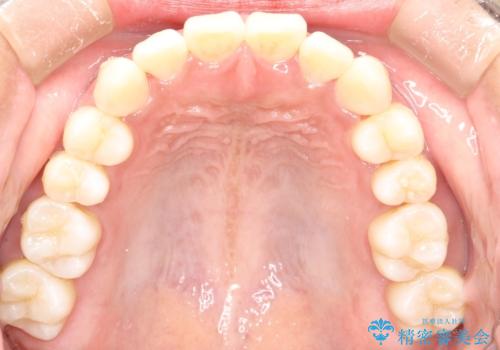

がたがたをインビザラインで整った歯並びへ

- 全体的ながたつきを主訴に来院されました。

抜歯矯正も考えられる状態でしたが、患者様が非抜歯での矯正を希望されたため、歯と歯の間をわずかに削りスペースを作り、全体を整える計画としました。